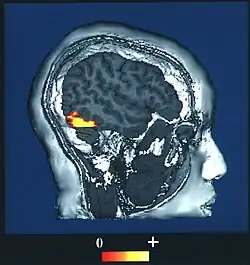

Computer-enhanced fMRI scan of a person who has been asked to look at faces. The image shows increased blood flow in cerebral cortex that recognizes faces (FFA).